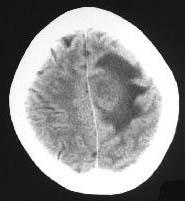

成年男性,头疼、头胀、发热,血象高,CT检查如图,选择最可能的诊断()A.脑脓肿B.胶质瘤C.皮样囊肿D.脑梗死E.脑膜瘤

问题 成年男性,头疼、头胀、发热,血象高,CT检查如图,选择最可能的诊断()

选项 A.脑脓肿 B.胶质瘤 C.皮样囊肿 D.脑梗死 E.脑膜瘤

答案 A